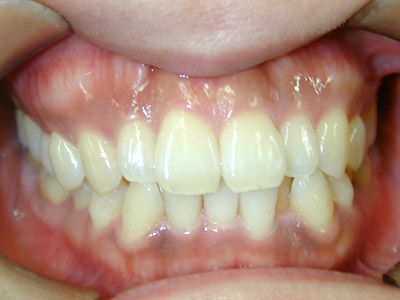

常滑市井戸田町在住 S.M様(23歳女性)

S.M様は口元の突出感と上顎前歯の傾きを主訴に当院の無料矯正相談にて来院されました。

診断の結果、咬み合わせが骨格的には反対咬合傾向の上下顎前突である事や前歯上顎前歯の歯軸が左右方向に流れて傾斜していること、

咬み合わせが浅いことなど治療はやや難度の高いことをお話しいたしました。

前歯の咬み合わせが浅く切端咬合です。上顎前歯の歯軸が左右的に傾いています。

犬歯関係・臼歯関係ともにClass3です。

犬歯関係、臼歯関係を咬み合わせが1歯対2歯のClass1に治療するためと口元の突出感を改善するために右側は上下顎第1小臼歯を抜歯しました。

左側は上顎第2小臼歯、下顎第1小臼歯を抜歯しました。

治療の経過で一時、反対咬合傾向がでましたが処置方針通り治療がすすみました。

S.M様は一度のキャンセルもなく予定通り来院治療され、

お渡ししてあった治療計画書通りに2年6ヶ月(30ヶ月)で動的治療を終えることができました。

治療期間:2年6ヶ月

治療費用:60万円